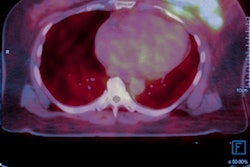

Pereira and colleagues conducted a study that used immune-PET and three antibodies to visualize three RTKs in a kidney tumor. The study showed that immune-PET could visualize the levels of protein present in an RTK, thus offering feedback on a tumor's response to therapy.